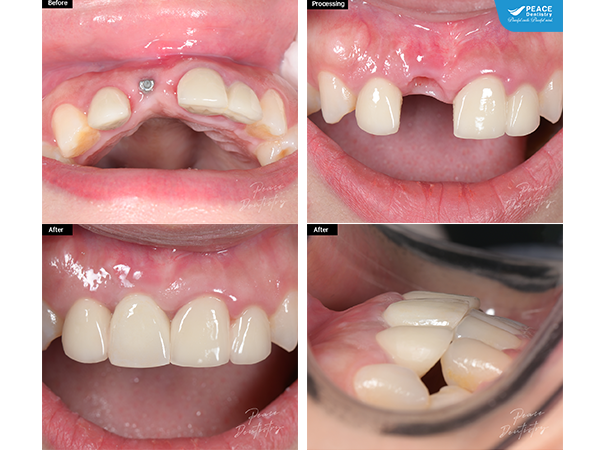

tháo bỏ cầu sứ R12-22 đã xuống cấp, nhổ chân răng R11 và cắm trụ Implant tức thì

(Ca lâm sàng tháo bỏ cầu sứ R12-22 đã xuống cấp, nhổ chân răng R11 và cắm trụ Implant tức thì. Sau đó tiến hành phục hình trên implant và bọc lại các răng đã mài để làm cầu răng sứ). Xem chi tiết ca lâm sàng tại đây (**)